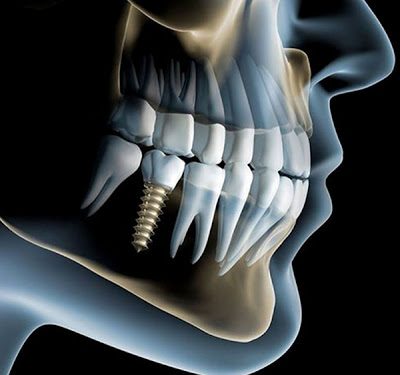

- Chirurgia Ossea Ricostruttiva per Inserimento Impianti

- Implantologia a Carico Immediato

- Metodica All-On-Four – Quattro Impianti a Protesi Avvitata

(ideale per persone edentule e per coloro che sono già portatori di protesi mobili)